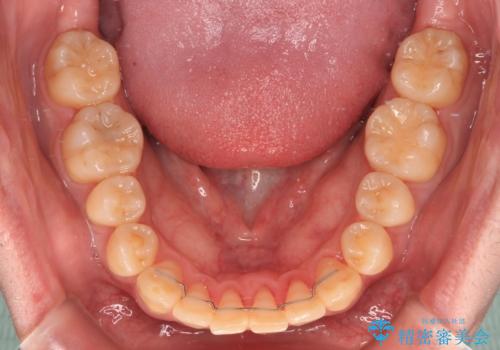

- 前歯のデコボコとクロスバイトを気にして来院された患者様です。

インビザラインでもワイヤー装置でも矯正治療は可能でしたが、煩わしい自己管理なしに短期間で治療を行いたいとのことで、目立たないワイヤー装置にて治療を行うこととしました。

- 1年1ヶ月